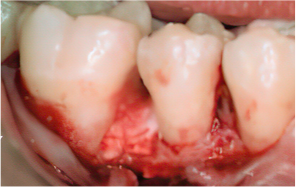

엠도게인 수술과정

STEP 04

엠도게인 도포

-

STEP 05

클렌징

STEP 06

판막을 봉합